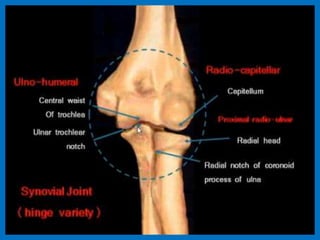

MRI of the elbow joint.